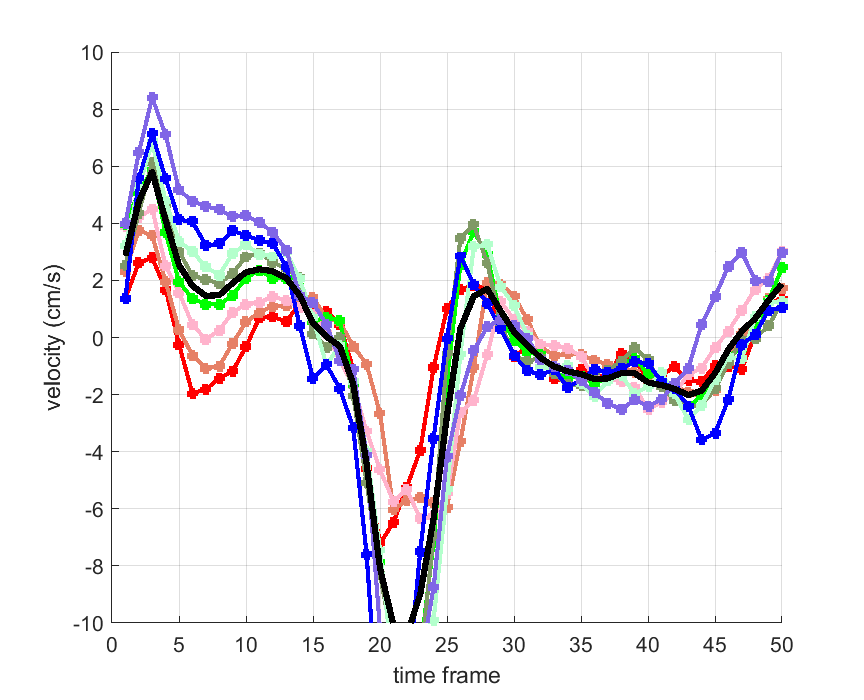

Time courses of the estimated translational component per subject, frame, slice and volume along the 3 velocity directions x, y and z are presented in Fig.6 - Fig.8.